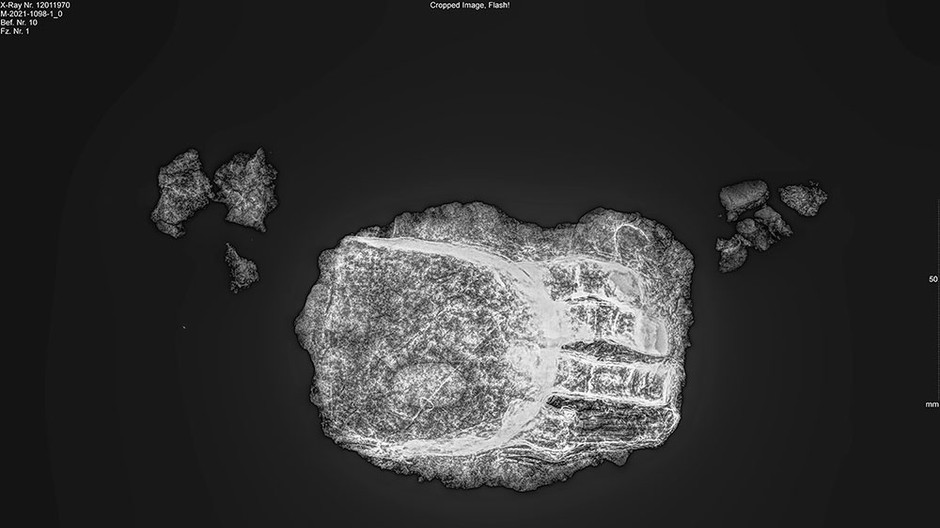

röntgen_hand_12011970

Zdroj: blfd.bayern.de

Archeológovia v Nemecku objavili takmer 600 rokov starú kostru s kovovou umelou končatinou. Podľa vyhlásenia Bavorského štátneho úradu pre ochranu historických pamiatok archeológovia použili datovanie pomocou izotopov uhlíka a odhadli, že muž mal pravdepodobne 30 až 50 rokov a zomrel v rokoch 1450 až 1620. Protéza bola vyrobená zo železa a nahrádzala štyri chýbajúce prsty.

Ukazovák, prostredník, prstenník a malíček boli vyrobené samostatne a nositeľ protézy nemohol žiadnym z nich pohybovať. Prsty protézy boli mierne zakrivené a navzájom rovnobežné. V protéze sa našla látka podobnej gáze, ktorú jej nositeľ pravdepodobne používal na zmiernenie deformácie ruky. Kostru našli archeológovia v bezprostrednej blízkosti kostola v meste Freising neďaleko Mníchova.